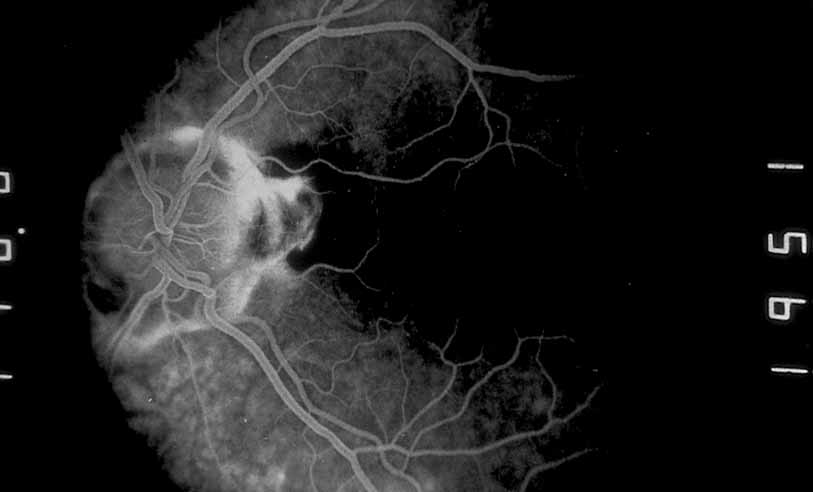

Fig. 10 Acute multifocal hemorrhagic retinal vasculitis. A middle-aged man presented with the picture of multiple branch vein obstructions and low-grade intraocular inflammation.

Fig. 11 Acute multifocal hemorrhagic retinal vasculitis. Fluorescein angiogram confirms the presence of associated retinal capillary non-perfusion without neovascularization at the onset of the disease.